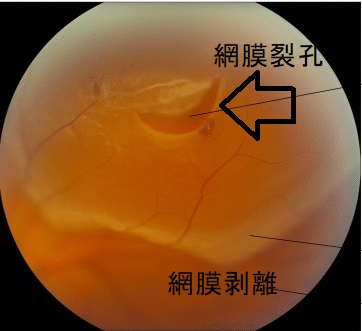

網膜裂孔(網膜の亀裂)の原因は、

(眼底写真;greeky medicsより改変)

網膜裂孔の症状は

- 飛蚊症

- 視力低下

- 光視症(白い光が見える)

- 昼盲(羞明のため)

網膜裂孔は細隙灯顕微鏡検査で前部硝子体に色素散布を認めます。

網膜裂孔は網膜剥離に進行するため光凝固療法の適応。